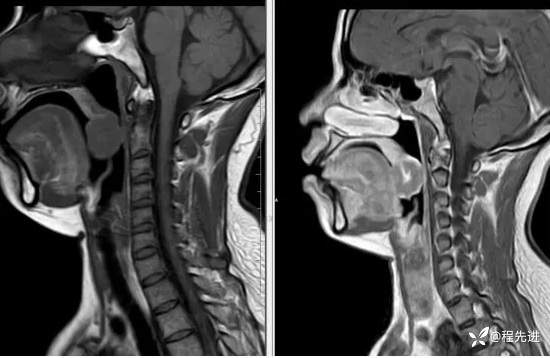

T2压脂、T1压脂增强: